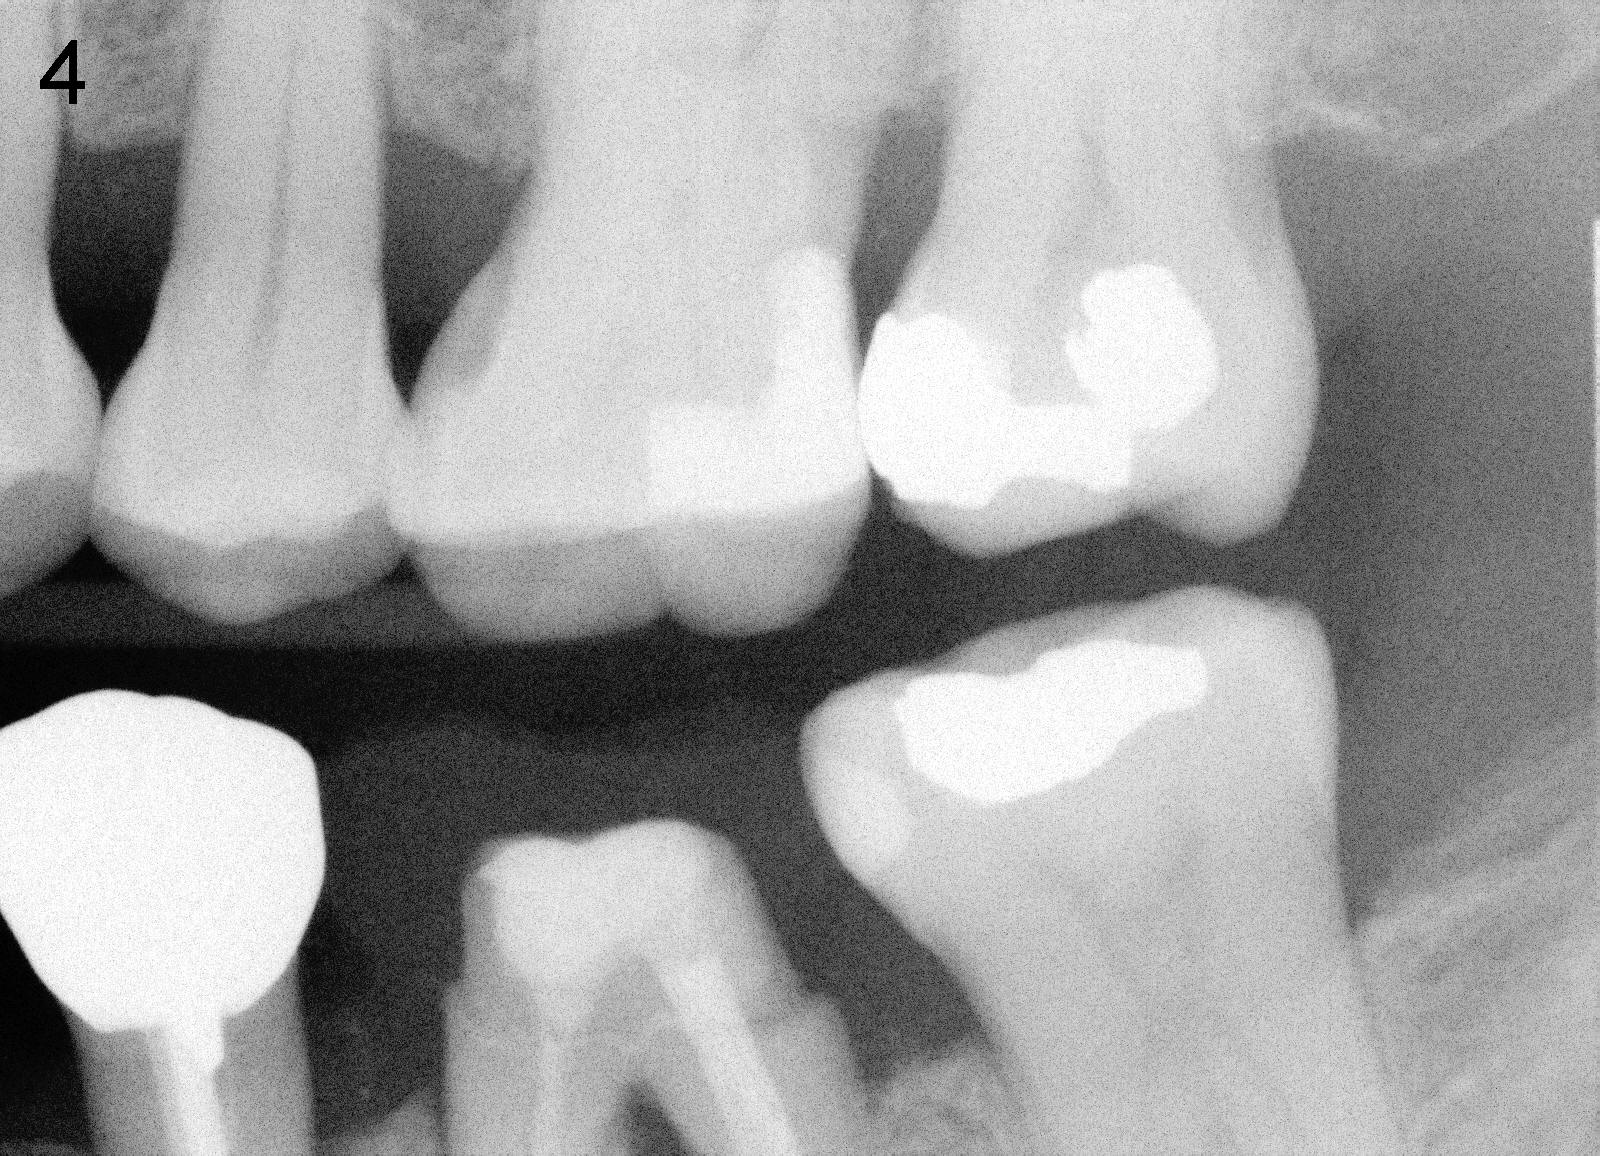

Bitewing and PAs for Upper Left Quadrant

X-ray was taken on 01/18/2010 (Fig.1) and 06/11/2011 (Fig.2-4). Clinically there is no gross lesion in the upper left quadrant, although pain is vague in position, according to the patient.

I think you have done a remarkable job. The mesial root is untreatable with the furcation and poor oral hygiene. I would advise the patient to keep cleaning the area with small brush and irrigate with salt water to furcation area. If pain persist and become intolerable, advice patient for extraction. I don't think she needs to see me at this time.